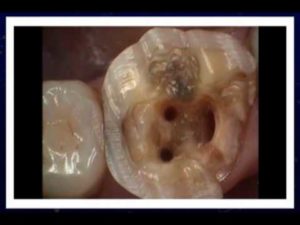

ROOT CANAL TREATMENT #Abscess #Infectionofrootcanal #Pain #Swelling

Root canal Procedure Step by Step | animation video|

Root Canals are EXTREMELY toxic – Dr. Mercola

Does Getting root canals hurt *ANSWER*